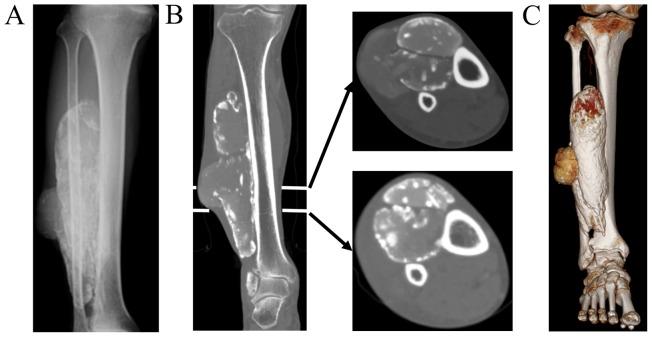

Calcific myonecrosis is a rare soft tissue condition. The first case was reported in 1960, however, the precise pathophysiology of calcific myonecrosis remains unclear. The disease was thought to arise from compartment syndrome within a confined space resulting in necrosis and fibrosis, subsequent repeated intralesional hemorrhage, mass enlargement and calcification. Several previous reports have described calcific myonecrosis, which include the formation of calcific myonecrosis after a prolonged period of post trauma. Notably, calcific myonecrosis has typically been described in the lower legs and characteristic imaging findings have been indicated. Furthermore, surgical intervention carries a high risk of complications. In the present case report 2 cases of calcific myonecrosis that occurred after a prolonged period of time following a traumatic event that impacted the lower leg were reported. CT images revealed disruption of calcified fascia and disease expansion into the outside of the fascia. Previous reports have implied that there is late focal enlargement of calcific myonecrosis following earlier enlargement, which may be caused by herniation through muscle fascia. However, no previous publications have focused on images for evidence of late local enlargement. To the best of our knowledge, this is the first report focusing on fascial herniation of calcific myonecrosis using images. Analysis of this feature using images may aid clinicians to differentiate calcific myonecrosis from malignancies.

钙化性肌坏死是一种罕见的软组织疾病。首例病例于1960年被报道,然而,钙化性肌坏死的确切病理生理学仍不清楚。该疾病被认为起因于有限空间内的骨筋膜室综合征,导致坏死和纤维化,随后反复的病灶内出血、肿块增大和钙化。此前有几篇报道描述过钙化性肌坏死,其中包括创伤后长时间形成的钙化性肌坏死。值得注意的是,钙化性肌坏死通常在小腿被描述,并且已经指出了其特征性的影像学表现。此外,手术干预具有较高的并发症风险。在本病例报告中,报道了2例在小腿受到创伤事件后很长一段时间发生的钙化性肌坏死病例。CT图像显示钙化筋膜中断,病变扩展至筋膜外。先前的报道暗示,钙化性肌坏死在早期增大后会出现晚期局灶性增大,这可能是由于通过肌肉筋膜的疝出所致。然而,以前没有出版物关注过晚期局部增大证据的图像。据我们所知,这是第一篇使用图像聚焦于钙化性肌坏死筋膜疝出的报告。利用图像对这一特征进行分析可能有助于临床医生将钙化性肌坏死与恶性肿瘤区分开来。